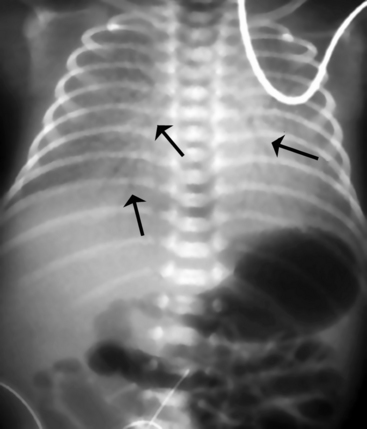

The newborn with diaphragmatic hernia may demonstrate severe respiratory distress. The chest radiograph reveals multiple abnormal air lucencies within the chest, usually the left hemithorax. This air is caused by the presence of loops of air-filled bowel in the chest (Fig. 10-6). The bowel compresses the lung on the involved side and shifts the mediastinum to the noninvolved (usually right) hemithorax, compressing that lung. Until the bowel fills with swallowed air, the newborn with a diaphragmatic hernia may be thought to have a mass in the left chest.

image image

Fig. 10-6 Congenital diaphragmatic hernia. A, This chest radiograph was obtained to evaluate a newborn admitted within the first few hours of life to the pediatric critical care unit with respiratory distress and poor feeding. The nasogastric tube can be traced into the left chest (arrow). The mediastinal structures are shifted to the right, and the dense opacity in the left hemithorax is due to the fluid filled stomach and loops of small bowel. There is no air in the stomach or small bowel. The newborn has a left congenital diaphragmatic hernia. B, This is a 2-day-old infant with a left congenital diaphragmatic hernia. There are multiple air-filled loops of bowel in the left hemithorax (arrows), with a marked shift of the mediastinum to the right. Note that in this case the nasogastric tube ends in the left upper quadrant of the abdomen, indicating that the stomach is in the abdomen and not in the chest.

(B, Radiograph courtesy of Sharon Stein, Nashville, TN.)